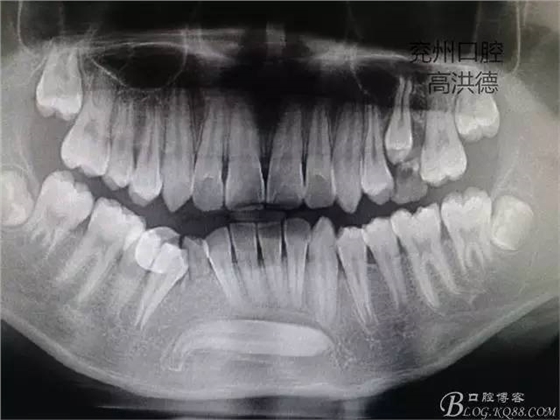

埋伏橫位3的取出術(shù)

患者閆XX,男,12歲

主訴:牙齒埋伏要求拔除

現(xiàn)病史:一周前,患者因乳牙不掉,影響進(jìn)食在外院拍攝X片,發(fā)現(xiàn)有牙齒埋伏,轉(zhuǎn)入我院要求拔除。

檢查:患兒面部對(duì)稱,開口度正常,混合牙列,右下乳磨牙,乳尖牙松動(dòng),下前牙萌出正常,前庭溝無隆起,無捫疼。

曲面斷層片顯示